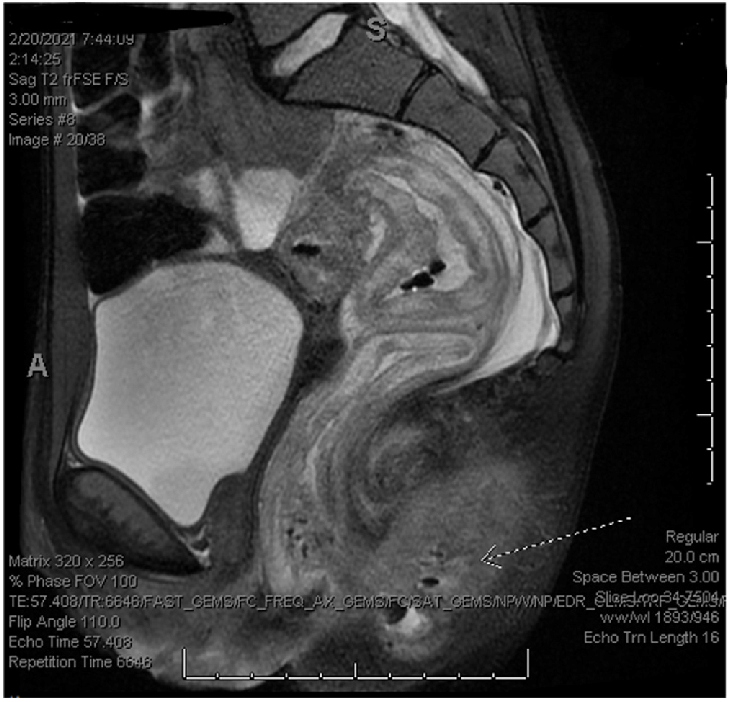

case of an acute onset ANCA positive vasculitis in an asymptomatic COVID-19 patient, resulting in significant colonic damage. she had blood in her urine, and was presented with worsening symptoms with significant necrosis of her perineum and rectum requiring surgical debridement and diverting colostomy.